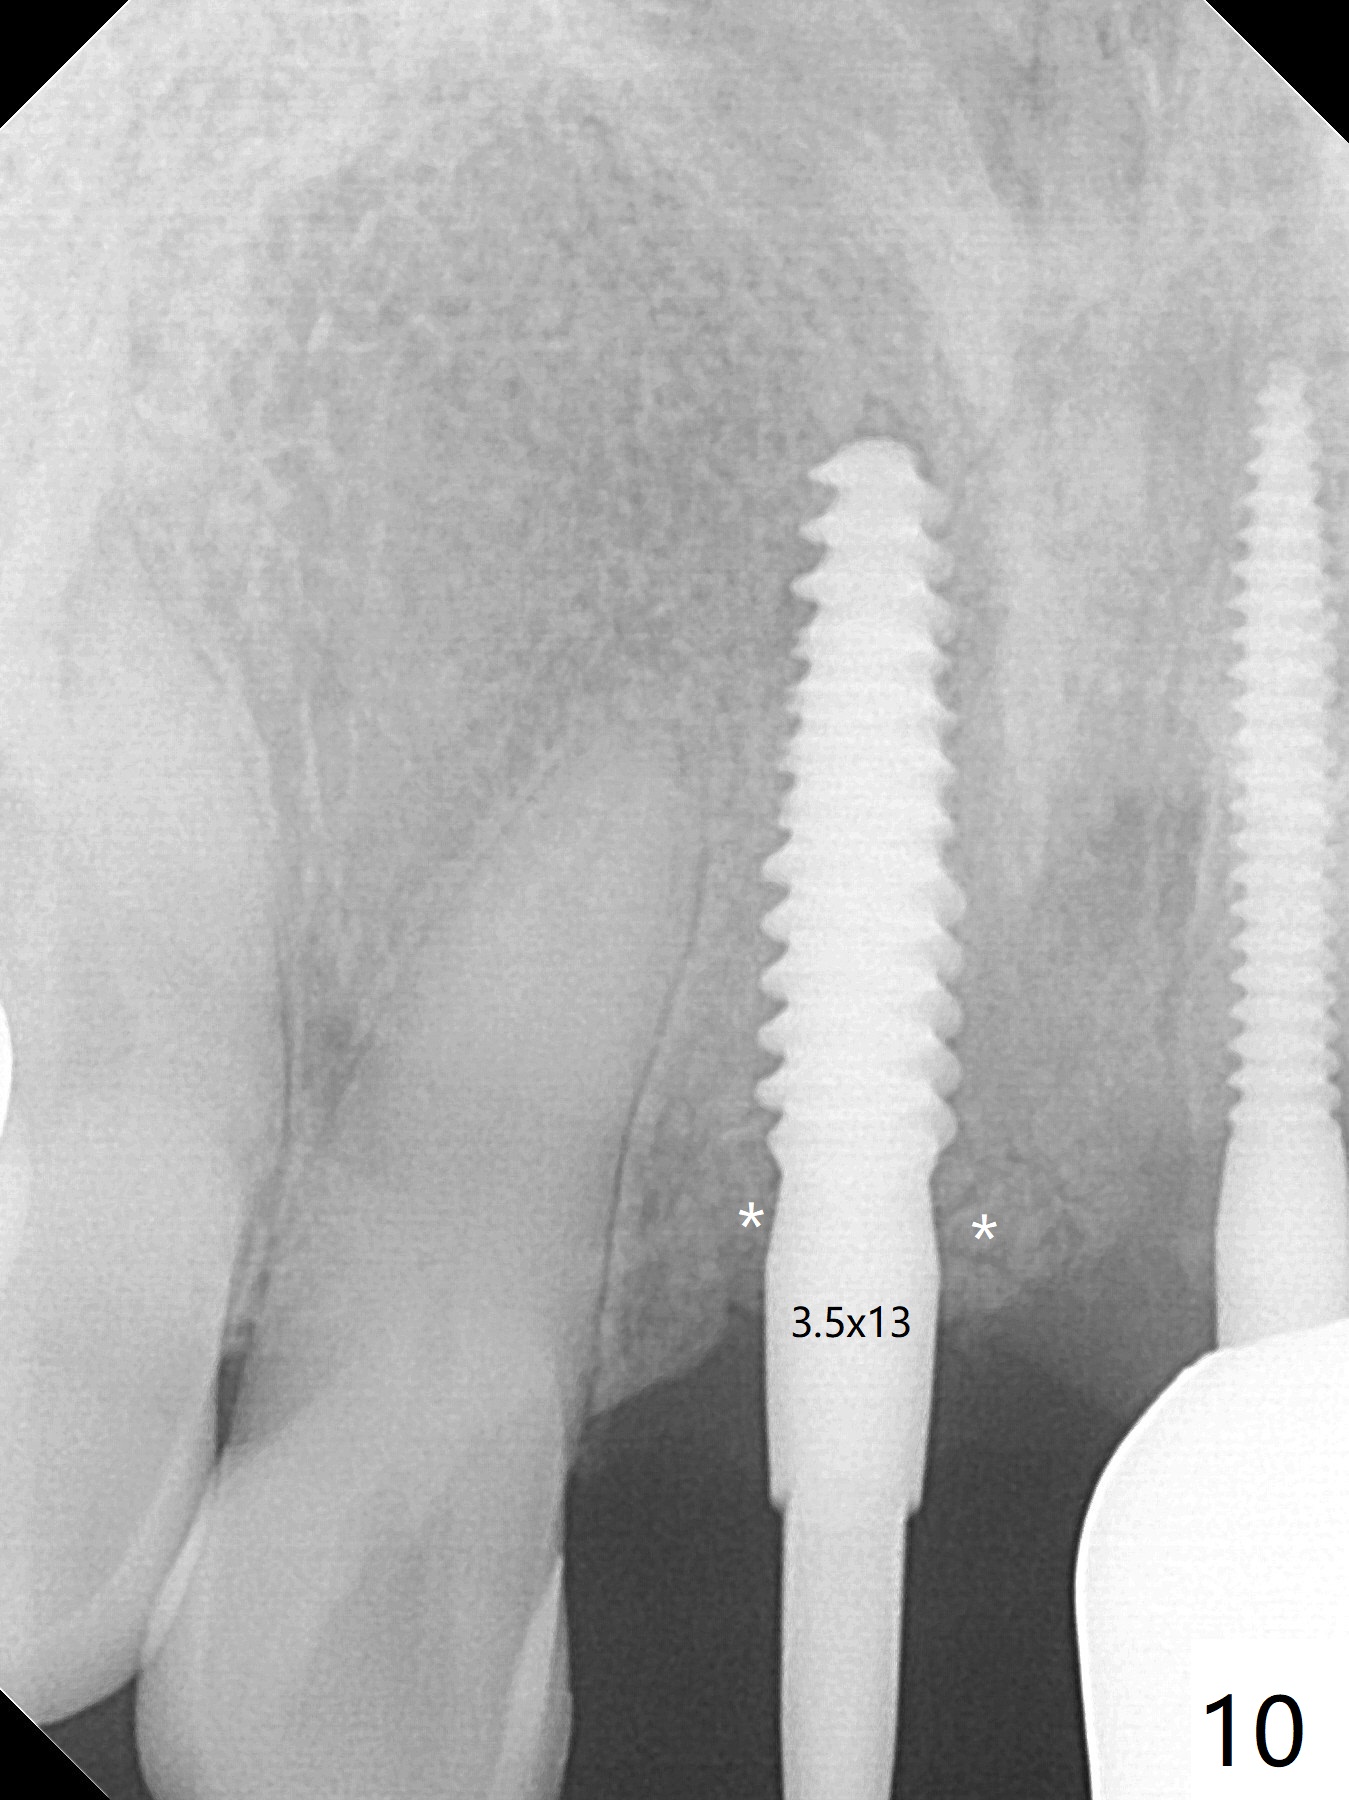

A 43-year-old man has 6 of 1-piece implants in the maxilla (#8-13). His daughter's head hits his upper anterior teeth 7 months post cementation. Exam shows that the tooth #7 has mild percussion. Nine months later the implant crown at #8 becomes displaced and loose when he bites apple (Fig.1 arrow). Forceps are used to remove the crown, leaving a concave implant site (Fig.2). After the crown is bonded to the neighboring tooth/implant crown (Fig.3 *), the patient feels pain from the neighboring tooth. The alveolus is 4.3 mm wide (Fig.4 (2.9 mm preop)), allowing 2.5 or 3.0 mm immediate implant re-placement (Fig.5). A 2.0/3.0 mm trephine bur will be used for implant removal. Try to place the new implant slightly distal to improve the trajectory (Fig.6). Particulate and/or onlay graft is an option. Prepare dummy implants. As planned, the fractured implant is removed by using a 2.0/3.0 mm trephine bur following incision (Fig.7). After use of Lindamann bur to remove the distal bone, a 3x14(4) mm dummy implant is placed with 20 Ncm (Fig.8). A longer implant could be used (3x16(2 or 4) mm), but a 3.5x13 mm 1-piece implant is placed with ~ 50 Ncm after use 3.0 mm drill (Fig.9,10). Allograft is placed around the implant (Fig.9,10 *), followed by Amnion-Chorion membrane and 5-0 PGA sutures (Fig.11). Allograft placed around the implant (Fig.9 *) appears to be able to prevent implant thread exposure 4 months postop (Fig.12). PA is taken when the crown is cemented (Fig.13). Four months postop cementation of #8 crown, the patient returns because of #9 mobility (Fig.14). In fact the implant fractures when the loose crown is removed with forceps; there is bone loss at #10. Bone graft will be placed at #10 with sticky bone (PRFx1), while the implant at #9 is redo. The ridge is wide enough for a 3.5x10 mm implant (Fig.16 (CT taken when #8 implant fractured)). Also prepare Tatum angled 1-piece implant. The 2 mm implant is too thin when occlusion contact at #10-13 is incomplete. The crowns will be redone when the implant at #9 is osteointegrated.